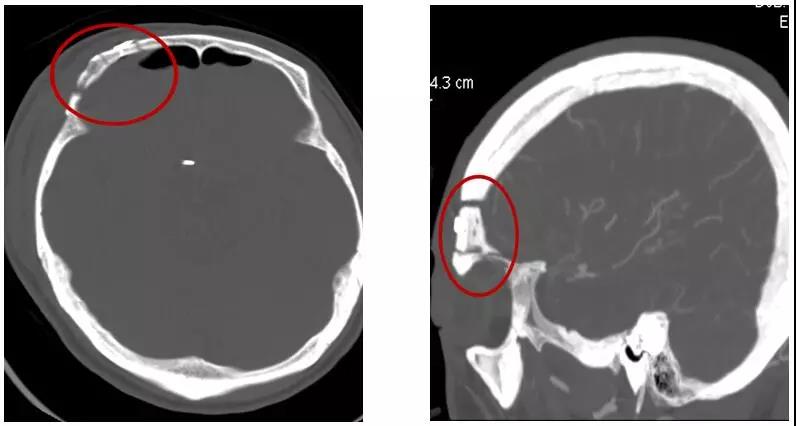

今年52岁的赖先生在外院检查发现颅内动脉瘤1周,为求进一步治疗前来惠州三院,头颅CTA检查提示:前交通动脉瘤。患者既往有糖尿病3年和高血压1年病史,未进行正规治疗和监测。

患者术前头部CTA

术后头部CT骨窗